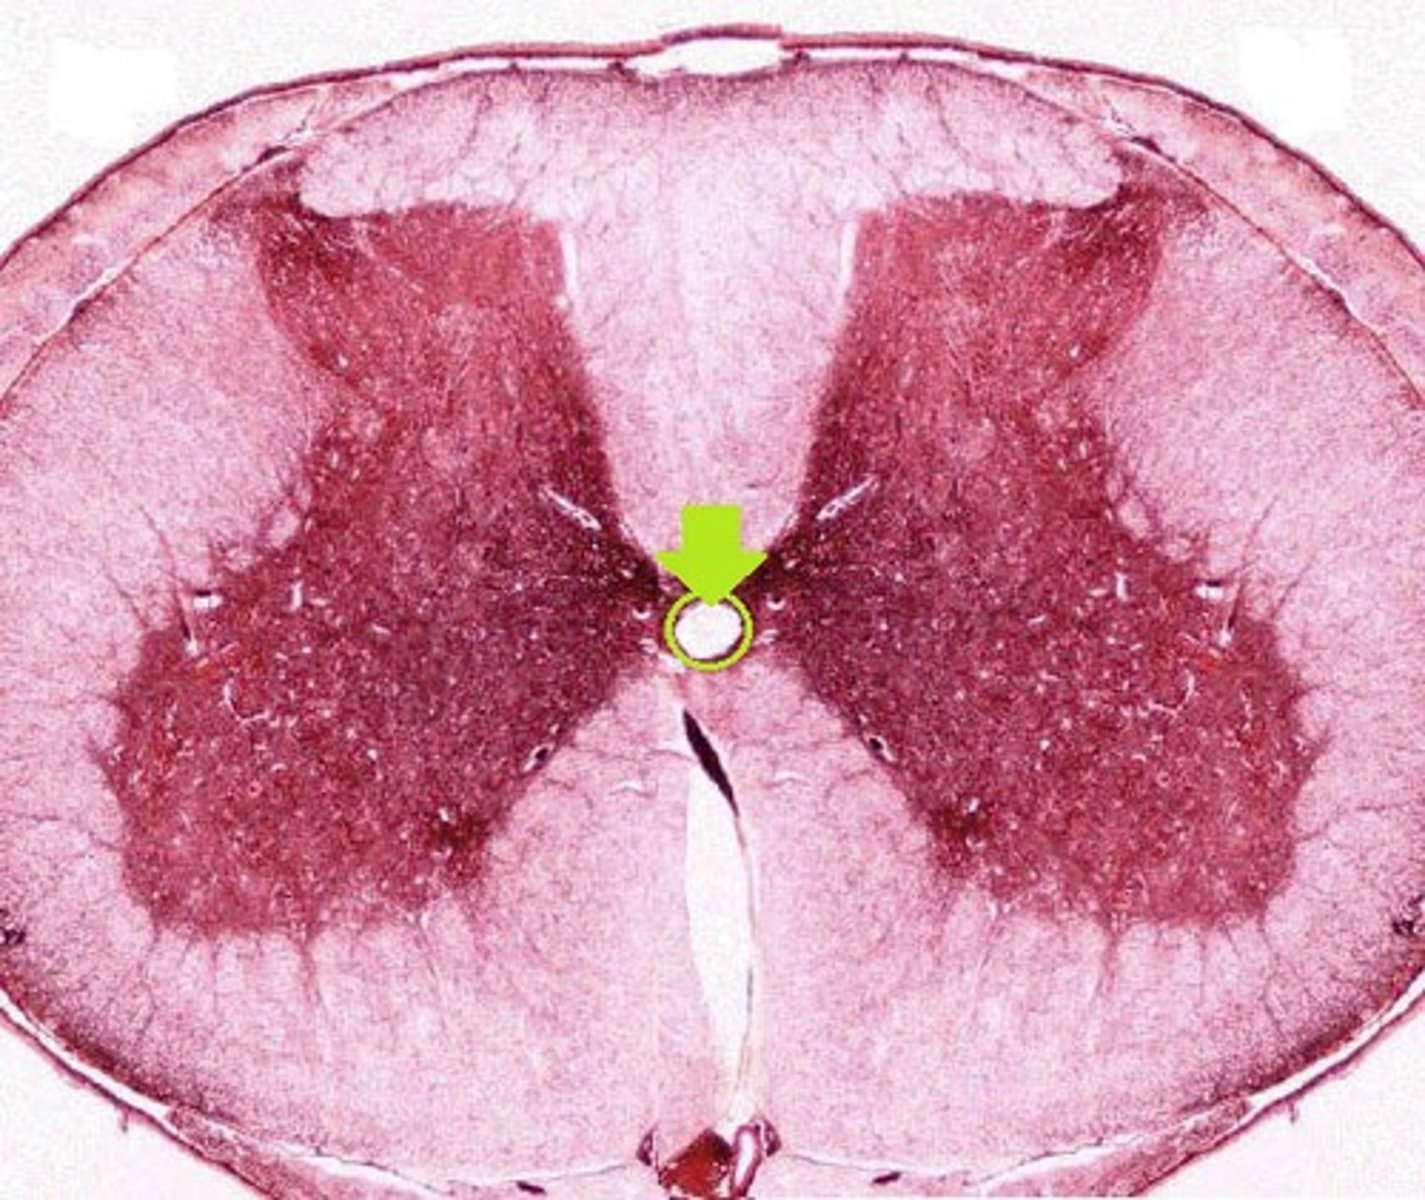

Anterior Gray Horn

Posterior Gray Horn (microscope slide spinal cord)

Anterior White Column

Posterior White Column (microscope slide spinal cord)

Motor Neurons (microscope slide spinal cord)

What neurons are found here?

Central Canal

Anterior Median Fissure

Posterior Median Sulcus